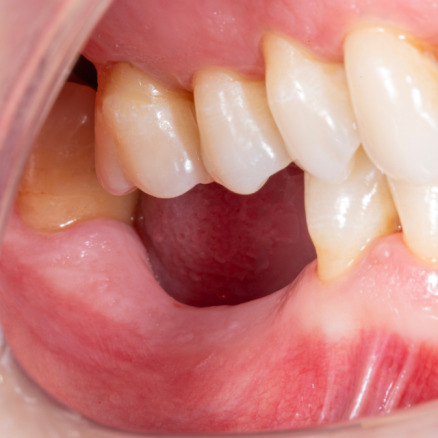

Diş çekiminin yıllar önce yapılmış olmasına bağlı olarak ince kemik varlığında implant ve kemik grefti uygulandı